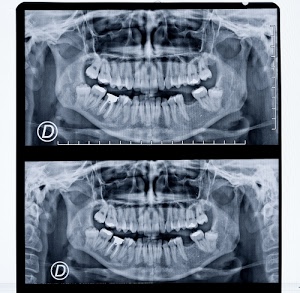

267° I raggi X o raggi Röntgen

Voto: 36.25 |